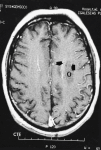

Fig. 3. Resonancia magnética nuclear (RMN) cerebral.